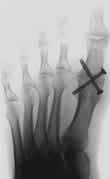

In Frage kommen bei weniger ausgeprägten Befunden Verkürzungsoperationen im Bereich des 1. Mittelfußköpfchens oder Großzehengrundgliedes, was zur Gelenkentlastung führt und dadurch die weitere Gelenkzerstörung aufhält.

Bei fortgeschritteneren Befunden entfernt man ggf. einen Teil des Gelenks und bildet ein "falsches" Gelenk aus. Straffes Bindegewebe zwischen den Knochenanteilen läßt meist eine ausreichende Beweglichkeit zu.

Möglich ist auch eine komplette Gelenkversteifung, was meistens zu vollständiger Beschwerdefreiheit führt, aber natürlich das Abrollverhalten des Fußes negativ beeinflusst.